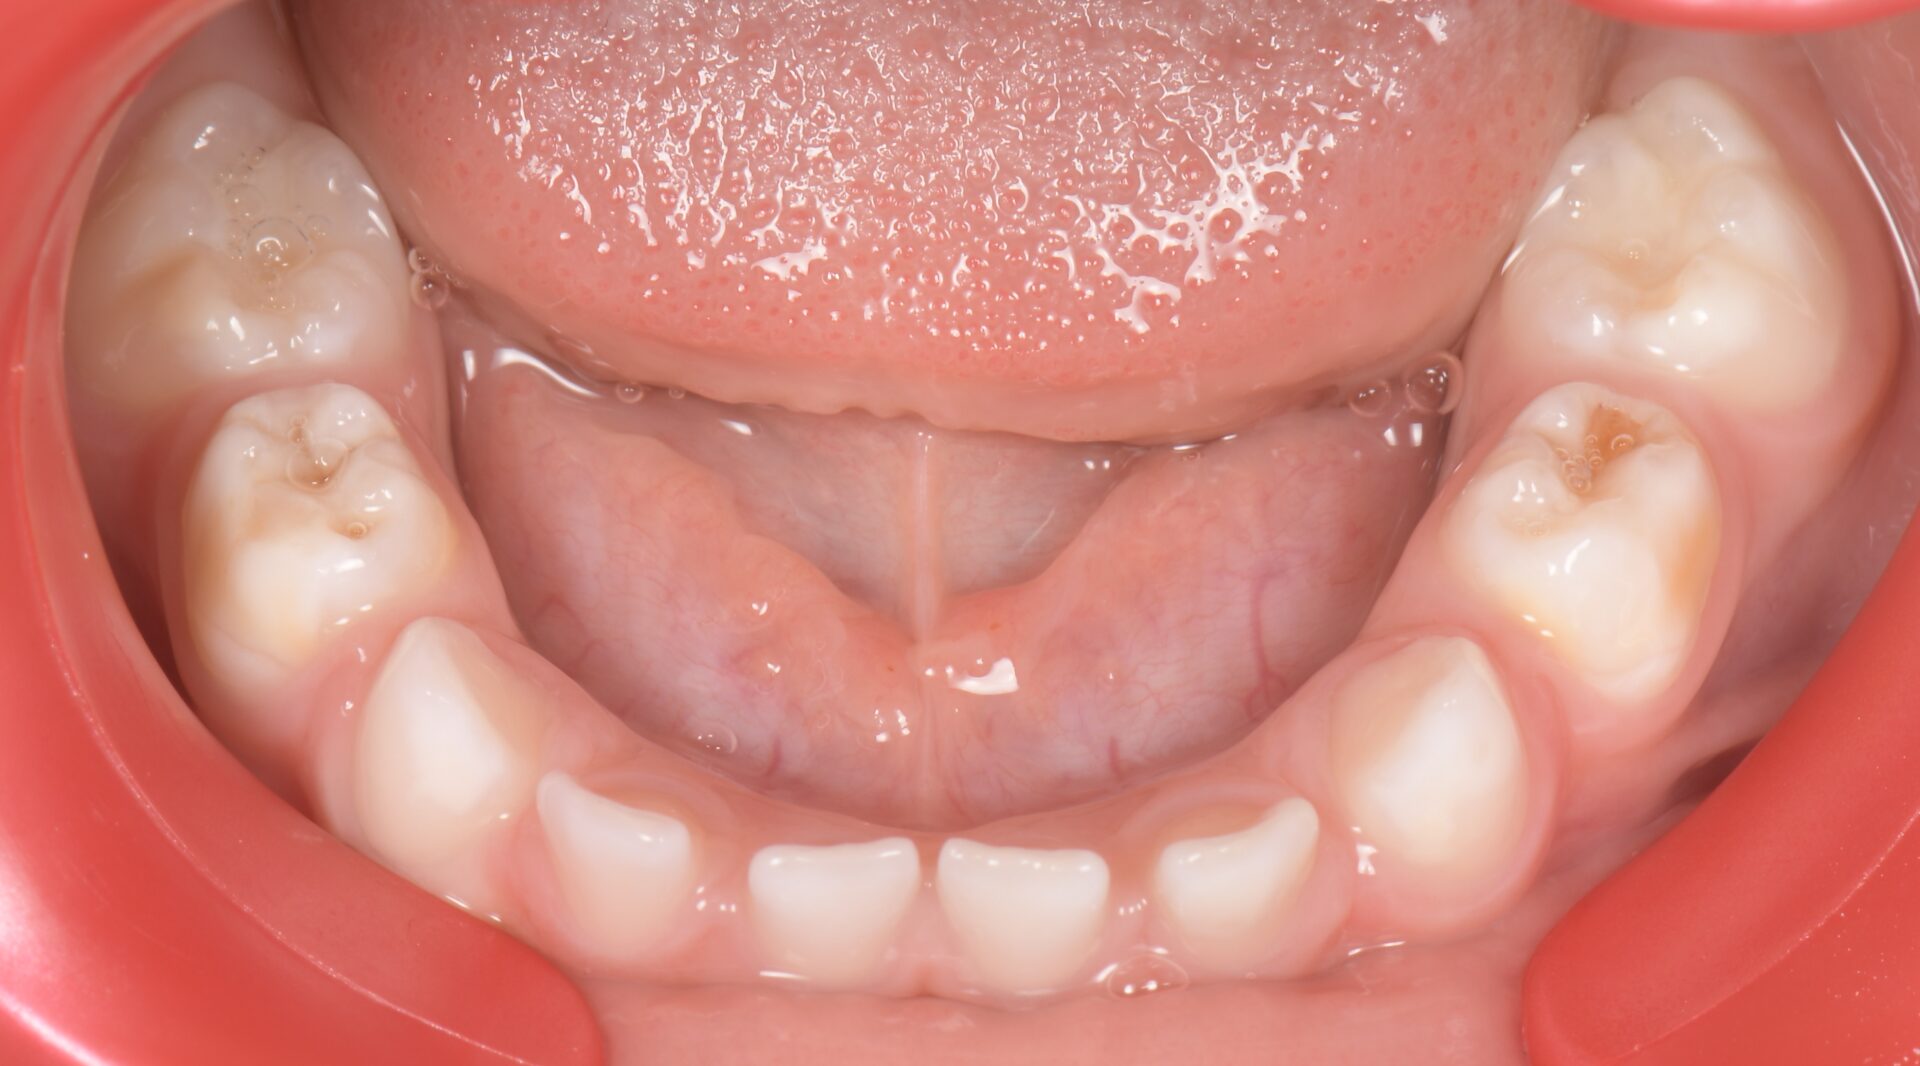

L’équivalent en denture temporaire est appelée HSPM pour Hypomineralised Second

primary Molar (Figures 5-6) (4).

formation dentaire pédodontie Figure 5.

formation dentaire pédodontie Figure 6.

Un enfant présentant une HSPM a 5 fois plus de risques de présenter également une MIH en denture permanente.

Figure 5-6 : Arcades maxillaire et mandibulaire d’un enfant atteint de HSPMfF